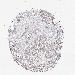

CANCER BREAST CANCER Show tissue menu

BRCA TCGA BRCA VALIDATION PROTEIN EXPRESSION